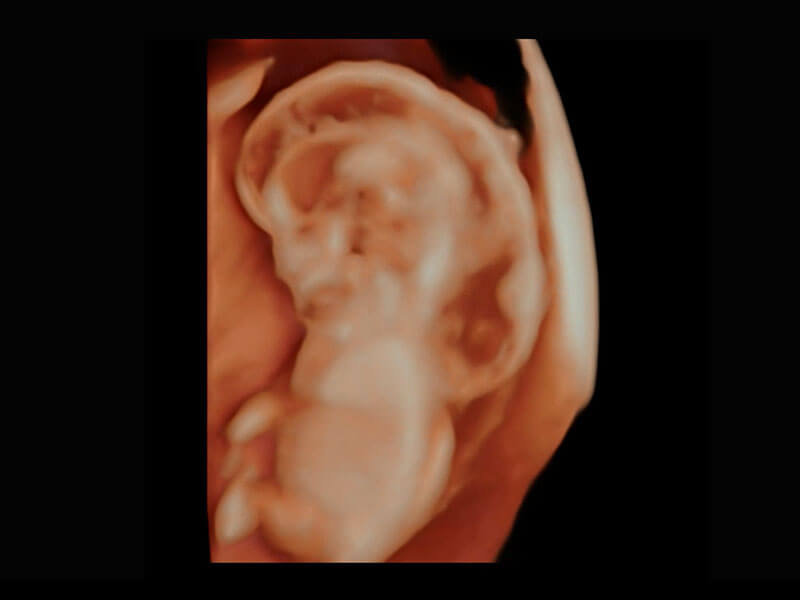

P60在胎儿早孕期超声筛查中为您带来优异的图像质量。

高分辨率容积成像-早孕胎儿

光影成像-孕囊